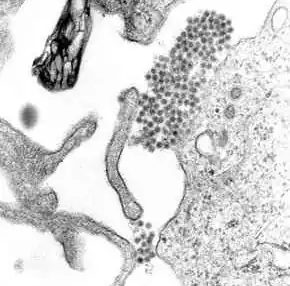

Uma microfotografia MET mostrando vírions do vírus da dengue (aglomerado de pontos escuros próximo ao centro).

O vírus da dengue (DENV) é um vírus RNA da família Flaviviridae; gênero Flavivirus. Entre outros membros do mesmo gênero estão os vírus da febre amarela, da febre do Nilo Ocidental, da encefalite de São Luís, encefalite japonesa, da encefalite transmitida por carrapatos, da doença da floresta de Kyasanur e da febre hemorrágica de Omsk. A maioria deles são transmitidos por artrópodes (mosquitos ou carrapatos) e, portanto, também são conhecidos como arbovírus, termo derivado da expressão em língua inglesa "arthropod-borne viruses".[11]